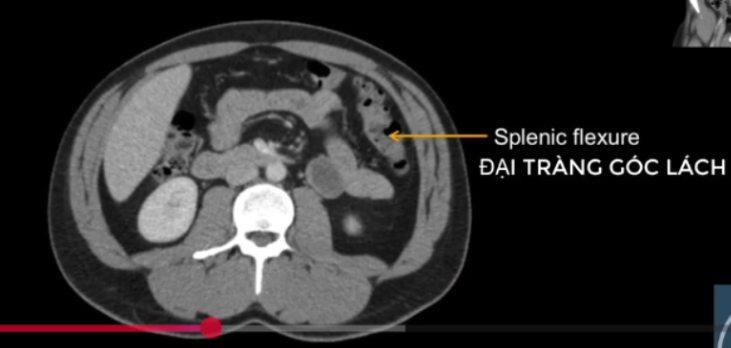

ĐT góc lách?